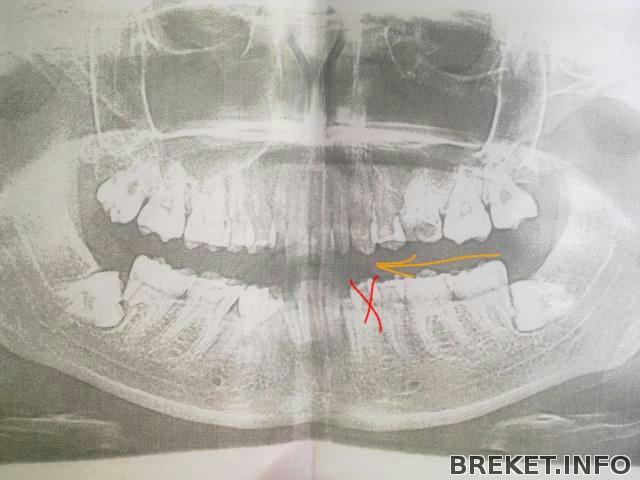

Предложила врачу "оттащить" семерку от восьмерки, такой путь спасения придумал один из хирургов. Правой семерки на НЧ я лишилась из-за того, что корни семерки протаранила ретенированная восьмерка, они рассосались. Восьмерку удалили, одноногая семерка не поняла, как так она осталась без опоры, да еще и со вскрытыми нервами снизу, решила воспалиться и пошла навылет. Теперь же мы попробуем разъединить семерку и восьмерку с левой стороны, надеюсь, что между ними сформируется костная ткань и поврежденный корень семерки останется в стерильных условиях во время и после удаления восьмерки. Это хоть какой-то шанс спасти мне зуб. Вот так вот должны двигаться семерка, шестерка и пятерка на место удаленной четверки